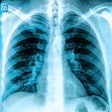

AI Trends in 2022: Thoracic Radiology